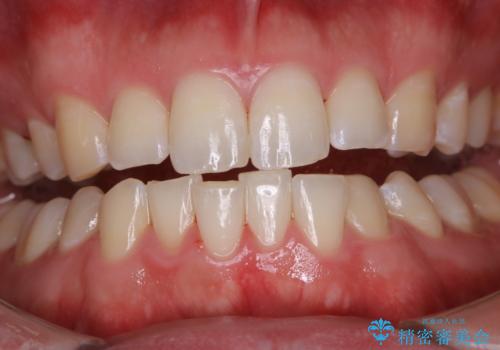

- 歯磨きをしても取れない汚れが気になるとのことで来院されました。PMTC60分コースを行いました。

歯周病やむし歯にならないように、定期的にプロフェッショナルケアを受け、お口の清潔を保つことが大切です。